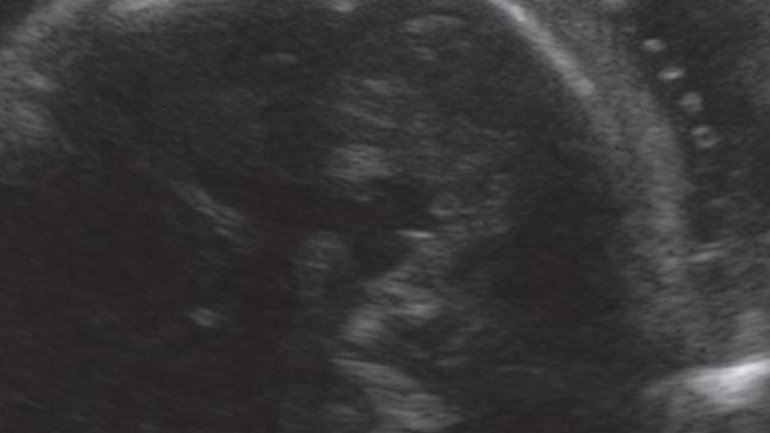

Ultraschall 27. SSW

Mit dem Dopplerultraschall kann auch der Blutfluss in den Blutgefäßen im Gehirn farbig dargestellt werden. Der*die Arzt*Ärztin überprüft so Reifung und Durchblutung des Gehirns und kann darüber bestimmte Krankheiten erkennen oder ausschließen.